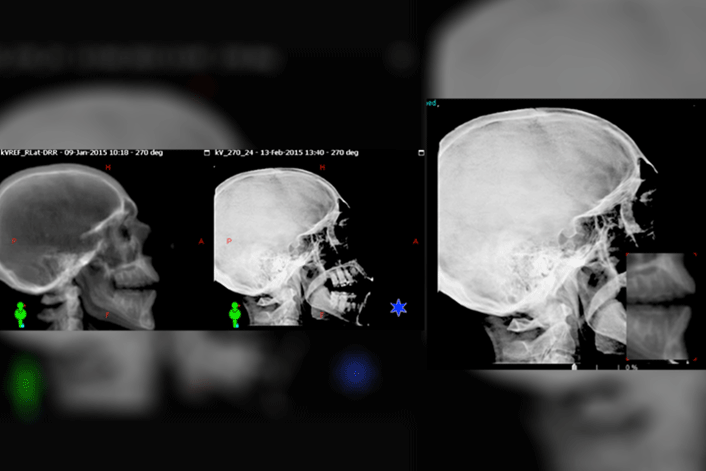

Now online in the Journal of Prosthodontics, Drs. Vincent Sung Kin Lee, Caroline Nguyen, and Jonn Wu present the results of a feasibility study to assess the effect of using a customized oral repositioning stent on patient positioning during the course of radiotherapy.

Radiotherapy is one of the main treatment modalities for head and neck cancers. To minimize damage to normal tissues during radiotherapy, various methods of stabilization have been used, including thermoplastic facemasks and repositioning stents. The authors of this study found that by using a customized repositioning stent, it was possible to maintain patient stability comparable to prior protocols and within the range of clinical guidelines, while providing superior comfort and ease of insertion to the patients.

Lee VS, Nguyen CT, Wu J: The fabrication of an acrylic repositioning stent for use during intensity modulated radiation therapy: A feasibility study. J Prosthodontdoi:10.1111/jopr.13074